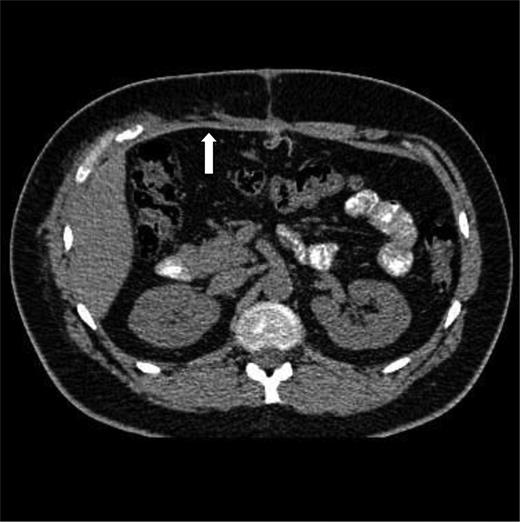

Six weeks after discharge, he was well with good mobility. He had a persistent seroma at the hernia site. A repeat CT of the thorax and abdomen at 10 weeks demonstrated no residual defect in the anterior abdominal wall and resolution of the seroma (Fig. 2).

CT at 10 weeks after the injury and primary repair. The mesh is seen in the anterior abdominal wall (arrow).